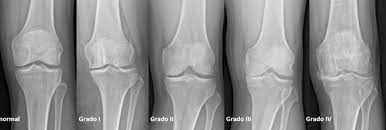

Terapia de ejercicio de dosis alta versus dosis baja para la osteoartritis de rodilla

27 enero 2023

Los resultados de este ensayo multicéntrico controlado aleatoriono respaldan la superioridad del ejercicio en dosis altas sobre el ejercicio en dosis bajas para la mayoría de los resultados. Sin embargo, se encontraron pequeños beneficios con altas dosis de ejercicio para la función de la rodilla en deportes y recreación y para la calidad de vida. Ann Intern Med, 24 de enero de 2023